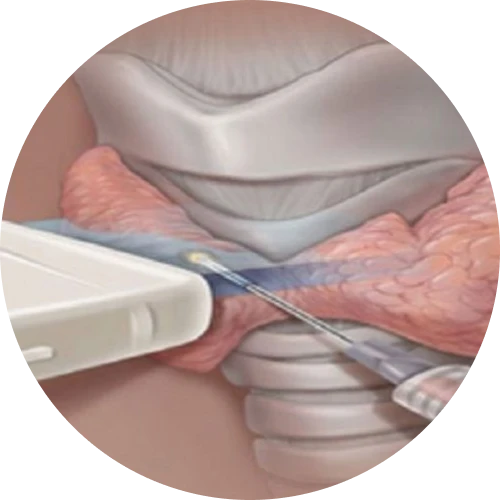

نمونه برداری fna

مرکز سونوگرافی دکتر سعید صادقی با بهرهگیری از تجهیزات پیشرفته و تکیه بر دانش تخصصی در حوزه تصویربرداری پزشکی، ارائهدهنده طیف کامل خدمات سونوگرافی بزرگسالان و اطفال است. در این مجموعه، انواع سونوگرافیهای عمومی و تخصصی، سونوگرافیهای داپلر رنگی و همچنین خدمات فوقتخصصی تیروئید، سر و گردن، پستان و کبد با دقت بالا و استانداردهای روز انجام میشود. این مرکز با رویکردی دقیق و علمی، سونوگرافیهای بارداری و آنومالی را با حساسیت ویژه برای پایش سلامت جنین ارائه میکند. انجام الاستوگرافی و فیبرواسکن کبد، نمونهبرداری و بیوپسی تودههای سر و گردن، تودههای پستان، ضایعات عضلانی–اسکلتی و نمونهبرداری FNA تیروئید نیز توسط دکتر صادقی با کمترین درد و بیشترین اطمینان انجام میگیرد. علاوه بر این، امکان مشاوره تخصصی در زمینه بررسی و تفسیر CT اسکن و MRI نیز برای بیماران فراهم شده تا مسیر تشخیص و درمان با اطمینان و آرامش بیشتری طی شود. ماموریت ما ارائه تصویربرداری دقیق، پاسخگویی مسئولانه و همراهی صمیمانه با بیماران است.

تیم پزشکی با صبر و حوصله علائم من را بررسی کردند و نمونهبرداری FNA بدون هیچ درد یا مشکلی انجام شد. نتایج به موقع ارائه شد و من حس امنیت و اعتماد کامل داشتم

برای من تشخیص زودهنگام توده گردن خیلی کمککننده بود. نمونهبرداری بدون درد و با دقت انجام شد و نتیجه به موقع آماده شد. واقعاً تجربهای مطمئن و حرفهای بود